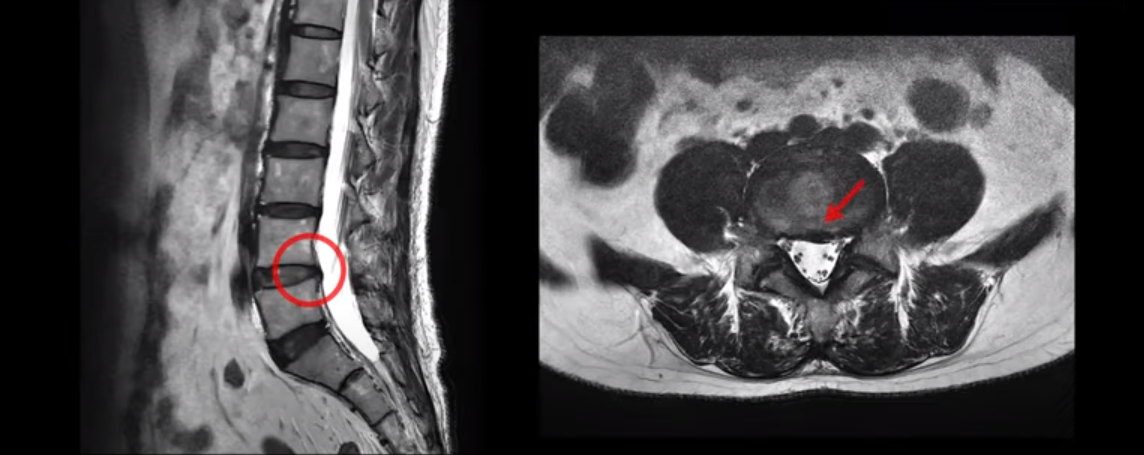

먼저 이분의 MRI 영상을 보면서 설명해 드린 후 환자분의 이야기를 직접 들어보시겠습니다.

보시는 것처럼 이 환자분의 4, 5번 디스크는 심하지 않습니다.

또한 신경이 나가는 구멍도 넓은 상태로, 신경을 누르고 있는 것도 보이지 않았습니다.